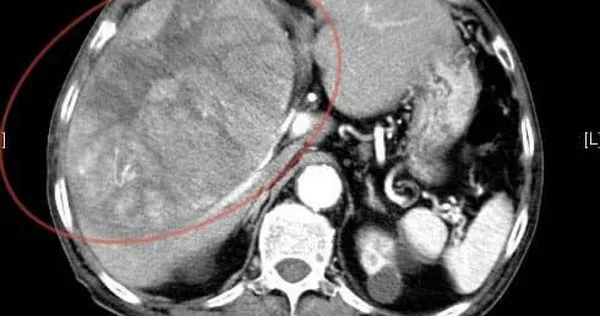

▲男子因上腹劇痛和胃酸逆流,超音波檢查發現,肝臟有15公分大腫瘤已癌末。(圖/翻攝自臉書/錢政弘 胃腸肝膽科醫師)

錢政弘透露,約2個多月前,阿公開始出現上腹疼痛和胃酸逆流,於是到他的門診求助,由於患者疼痛的部位偏右上腹部,且右側肋骨下方有壓痛,初步懷疑是膽囊問題,於是安排腹部超音波檢查,結果發現肝臟有個15公分大的腫瘤,後續CT檢查證實已經是晚期肝癌,無法手術,治療沒多久就離世了。